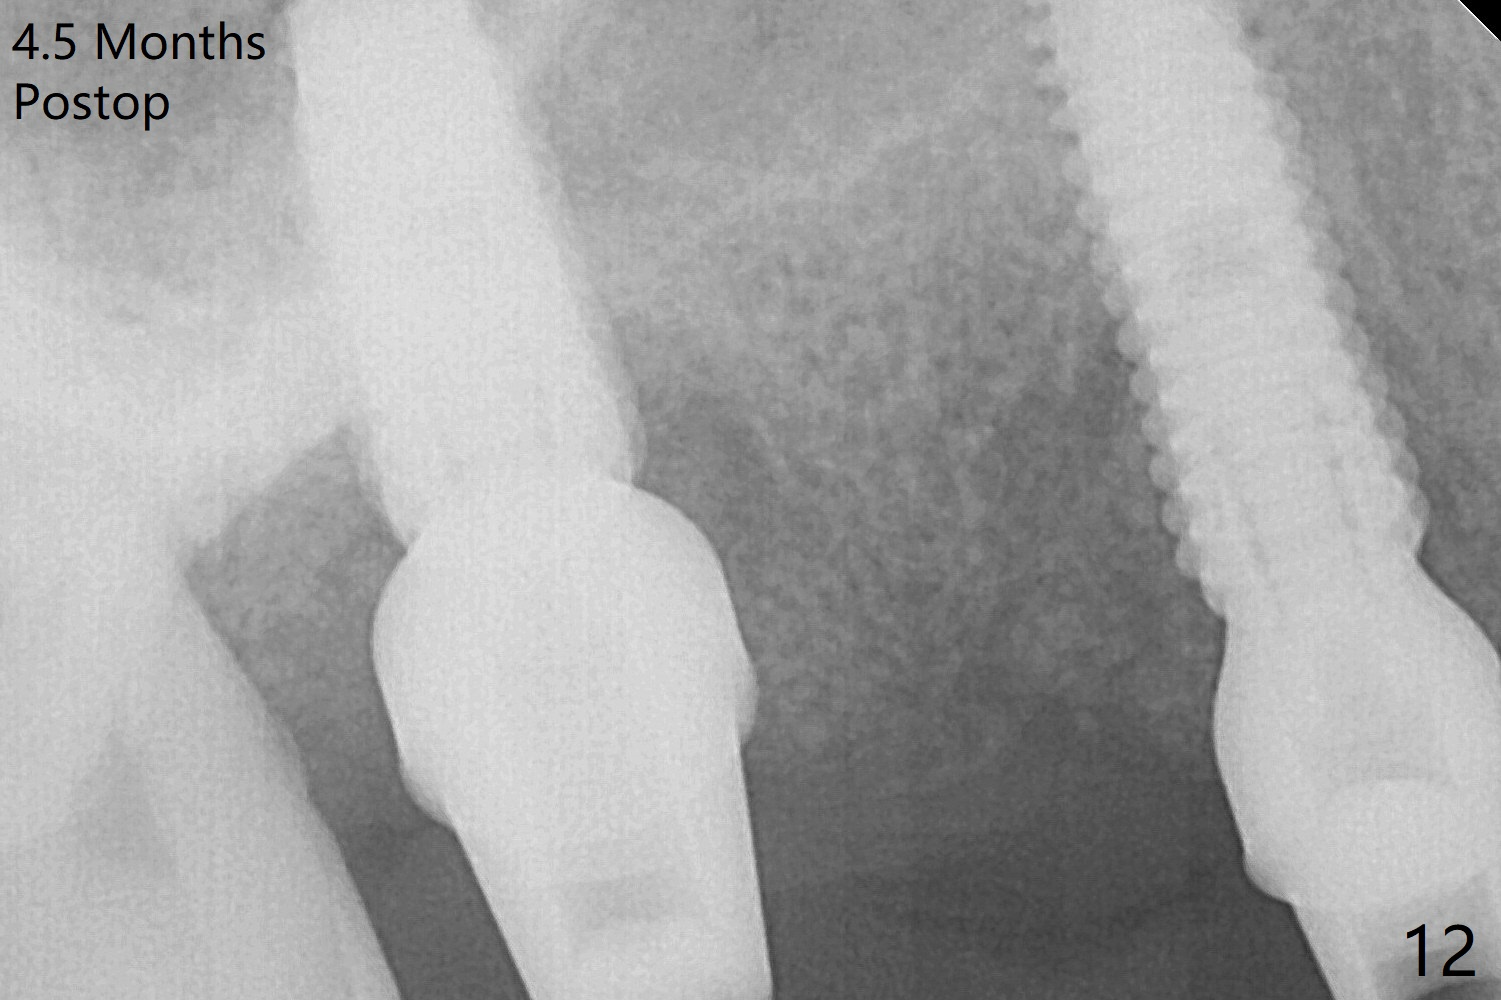

The implant at #5 is seated ~1 mm deeper (subcrestal mesially (^^); supracrestal distally (^)); allograft is placed around the implants prior to insertion of 6.5x7(5) and 5.5x4(5) mm abutments; last more allograft is added (Fig.9 *, 10). There is a large space buccally at #3 and 5, since the implants are placed palatally. Osteogen plug is placed buccally prior to placement of bone graft around the implants. The implants seem to have been osteointegrated 4.5 months postop (Fig.12). The gingiva is healthy around the implants without bone loss 3 months post cementation (Fig.13,14).